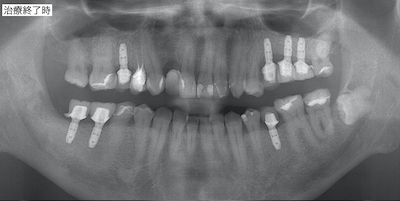

初診時と術後のレントゲンです。

抜歯、骨組織再生処置を終え、インプラントとアンカースクリューを必要箇所に全て埋入しました。

治療内容:骨組織再生後、7本のインプラントを埋入。仮歯作成後、光学印象、セラミッククラウン装着。